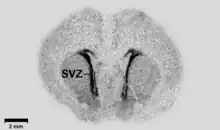

Autoradiography of a coronal brain slice, taken from an embryonal rat. GAD67-binding marker is highly expressed in the subventricular zone.